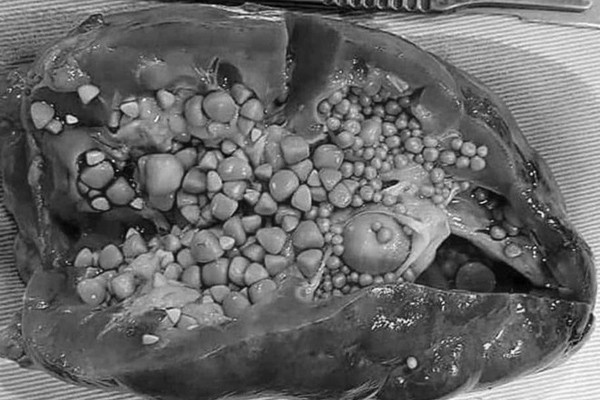

Sỏi tiết niệu là bệnh lý rất phổ biến, nếu để lâu, nhu mô thận sẽ bị giãn mỏng, mất chức năng.

Theo PGS Thành, sỏi tiết niệu là bệnh lý cực kỳ phổ biến, chiếm 45 - 50% các bệnh tiết niệu ở Việt Nam, trong đó nam giới chiếm 60%. Riêng tại BV Việt Đức, mỗi ngày tiếp nhận 25 - 30 bệnh nhân bị sỏi thận.

Trong nhiều năm làm nghề, PGS Thành đã từng phẫu thuật cho nhiều trường hợp bị sỏi thận kích cỡ lớn, tương đương quả cam, quả bưởi, nhưng nhiều năm trở lại đây, số ca bị “sỏi khổng lồ” đã giảm dần.

Khi để muộn, sỏi đài bể thận sẽ gây biến chứng như: Nhiễm khuẩn tiết niệu; viêm đài bể thận, viêm thận kẽ, viêm hẹp cổ đài thận; giãn đài bể thận, ứ nước, ứ mủ thận, áp xe thận; viêm quanh thận xơ hoá; cao huyết áp do sỏi san hô thận gây thiếu máu nhu mô thận, teo thận; suy thận do sỏi thận 2 bên gây tắc nghẽn...